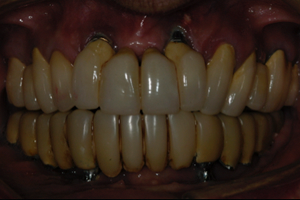

Figuras 5 e 6 – Aspecto clínico e radiográfico de reabilitação com implantes osseointegrados superiores e subperiósteos (justaósseos) inferiores. Estes com 30 anos de função.